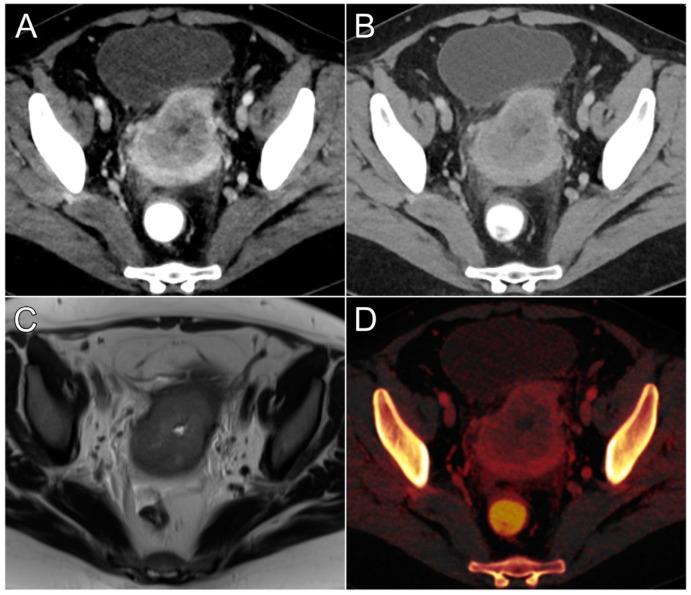

This study investigated whether virtual monoenergetic images (VMIs) and iodine mapping based on dual-energy CT (DECT) provide advantages in the assessment of endometrial cancer. A dual-source DECT was performed for primary staging of histologically proven endometrioid adenocarcinoma in 21 women (66.8 ± 12.0 years). In addition to iodine maps, VMIs at 40, 50, 60, 70, and 80 keV were reconstructed from polyenergetic images (PEIs). Objective analysis comprised the measurement of tumor contrast, contrast-to-noise ratio, and normalized iodine concentration (NIC). In addition, three radiologists independently rated tumor conspicuity. The highest tumor contrast (106.6 ± 45.0 HU) and contrast-to-noise ratio (4.4 ± 2.0) was established for VMIs at 40 keV. Tumor contrast in all VMIs ≤ 60 keV was higher than in PEIs ( < 0.001). The NIC of malignant tissue measured in iodine maps was substantially lower compared with a healthy myometrium (0.3 ± 0.1 versus 0.6 ± 0.1 mg/mL; < 0.001). Tumor conspicuity was highest in 40 keV datasets, whereas no difference was found among PEIs and VMIs at 60 and 70 keV ( ≥ 0.334). Interobserver agreement was good, indicated by an intraclass correlation coefficient of 0.824 (0.772-0.876; < 0.001). In conclusion, computation of VMIs at 40 keV and color-coded iodine maps aids the assessment of endometroid adenocarcinoma in primary staging.

本研究调查了基于双能CT(DECT)的虚拟单能量图像(VMI)和碘图在子宫内膜癌评估中是否具有优势。对21名组织学证实为子宫内膜样腺癌的女性(66.8±12.0岁)进行了双源DECT检查以进行初步分期。除碘图外,还从多能图像(PEI)重建了40、50、60、70和80 keV的VMI。客观分析包括测量肿瘤对比度、对比噪声比和归一化碘浓度(NIC)。此外,三名放射科医生独立对肿瘤的可辨识度进行评分。40 keV的VMI具有最高的肿瘤对比度(106.6±45.0 HU)和对比噪声比(4.4±2.0)。所有≤60 keV的VMI中的肿瘤对比度均高于PEI(<0.001)。碘图中测量的恶性组织的NIC与健康子宫肌层相比显著更低(0.3±0.1对0.6±0.1 mg/mL;<0.001)。40 keV数据集中肿瘤的可辨识度最高,而在60和70 keV时PEI和VMI之间未发现差异(≥0.334)。组内相关系数为0.824(0.772 - 0.876;<0.001),表明观察者间一致性良好。总之,40 keV的VMI计算和彩色编码碘图有助于子宫内膜样腺癌的初步分期评估。